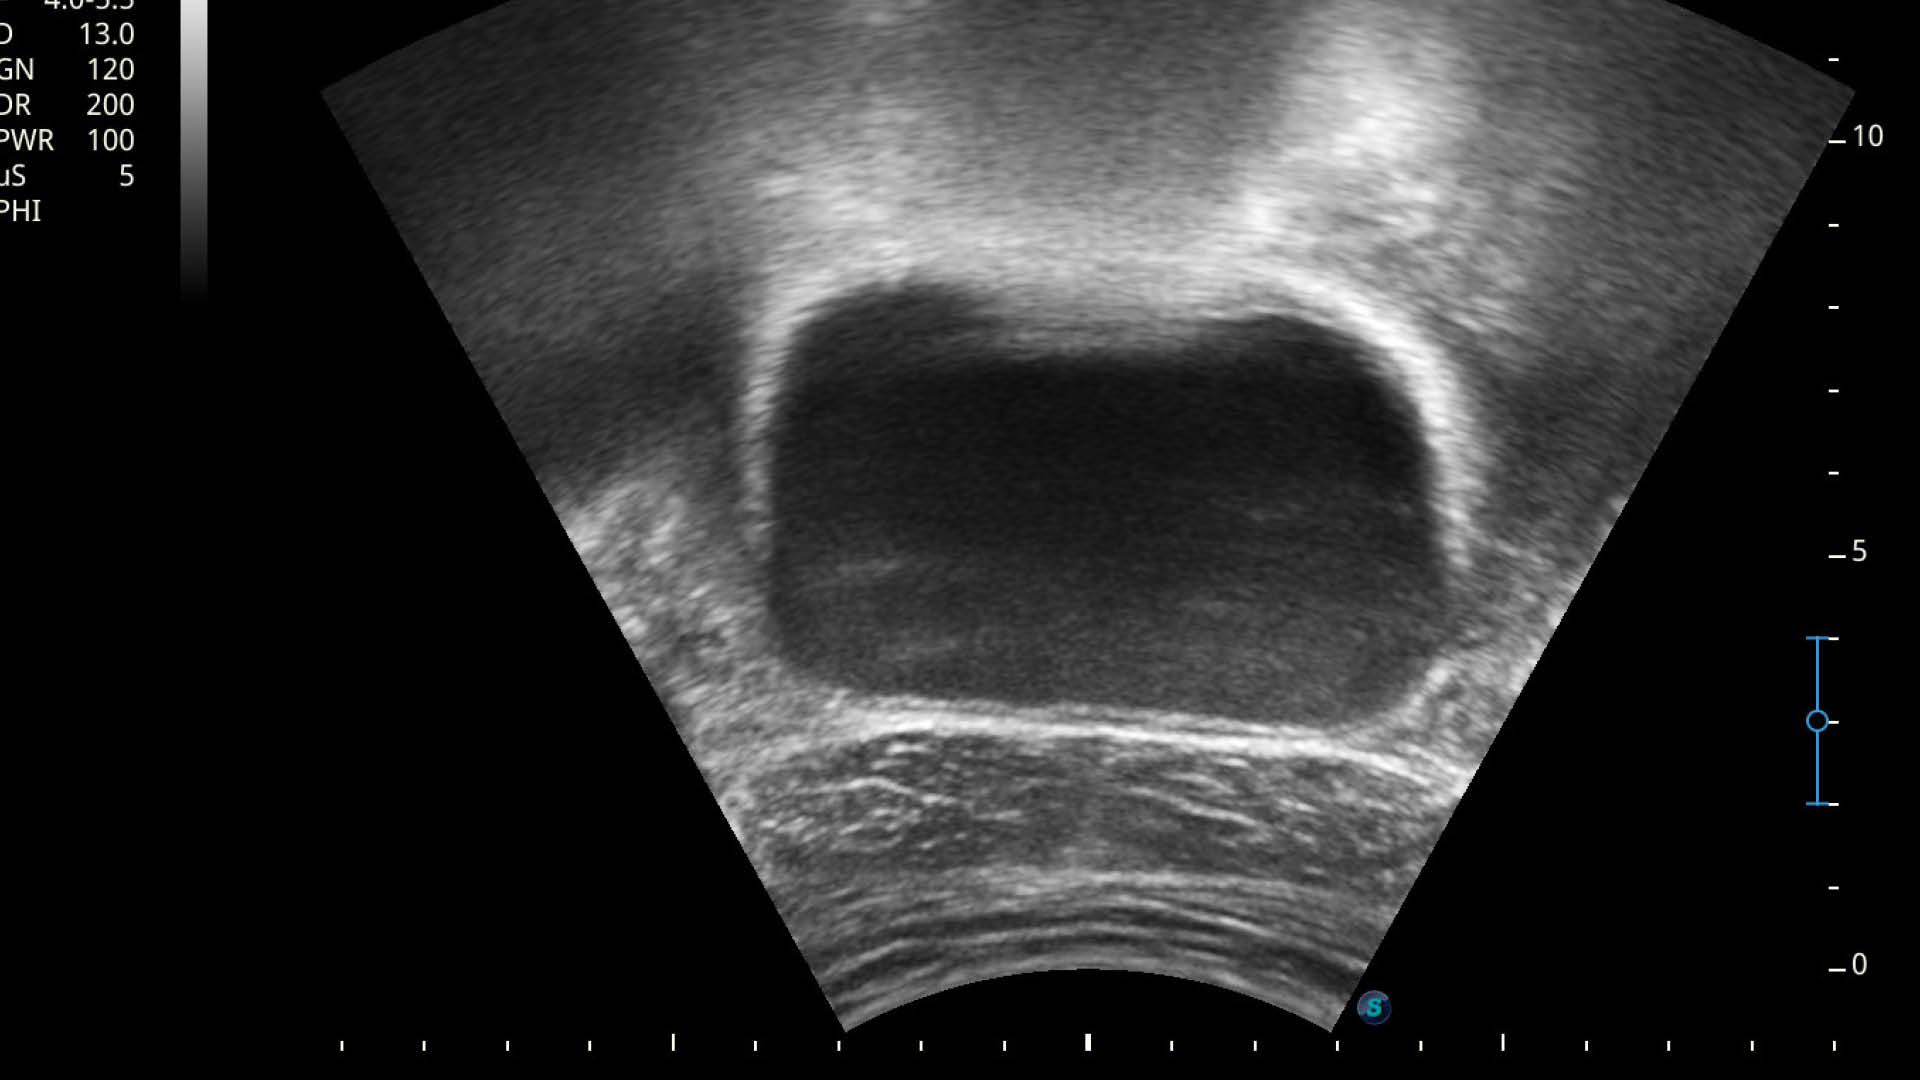

Während Biofeedback-Methoden wie Druck- oder Oberflächen-Elektromyografie (EMG) schon lange in der Beckenbodentherapie zum Einsatz kommen, setzt die praxis entero in Graz auf einen revolutionären Ansatz: Echtzeit-Ultraschall (EZUS) als Biofeedback-Methode.

1. Visuelles Feedback in Echtzeit: Wolfgang Brunner-Fruhmann setzt einen Ultraschallkopf auf euren Damm-Bereich. Auf einem Bildschirm seht ihr live, wie sich die Muskulatur bewegt, wenn ihr den Beckenboden anspannt oder entspannt. Außerdem kann man dabei beobachten, wie sich auch die umliegenden Strukturen, wie zum Beispiel die Harnröhre bewegen und die Position verändern. Ein wesentlicher Faktor für die Kontinenz.

2. Präzision und Korrektur: Ihr erhaltet eine sofortige, visuelle Rückmeldung über die Qualität eurer Muskelaktivierung. Ist die Anspannung korrekt? Haltet ihr die Luft an? Spannt ihr zu stark oder zu schwach an? Kompensiert ihr mit anderen Muskeln? Der Therapeut kann euch sofort korrigieren und ihr seht euren Fortschritt auf dem Bildschirm.

3. Schnellerer Lernerfolg: Die visuelle Darstellung fördert das Körpergefühl und die neurologische Ansteuerung der Muskulatur immens. Was vorher abstrakt war, wird sichtbar. Das Gehirn lernt durch dieses klare Feedback deutlich schneller, die wichtigen Muskeln isoliert und effektiv anzusteuern.

4. Motivation und Kontrolle: Ihr seht eure Erfolge schwarz auf weiß bzw. in Graustufen auf dem Bildschirm. Das ist ein riesiger Motivationsfaktor und gibt euch ein Gefühl der Kontrolle über euren Körper zurück.

„Mit dem Echtzeit-Ultraschall nehmen wir unseren Patienten die Unsicherheit. Sie sehen, wie die tiefen Beckenbodenstrukturen arbeiten. Wir überspringen damit oft langwierige Phasen der reinen Wahrnehmungsschulung und kommen schneller zur effektiven Kräftigung“, betont Wolfgang Brunner-Fruhmann.